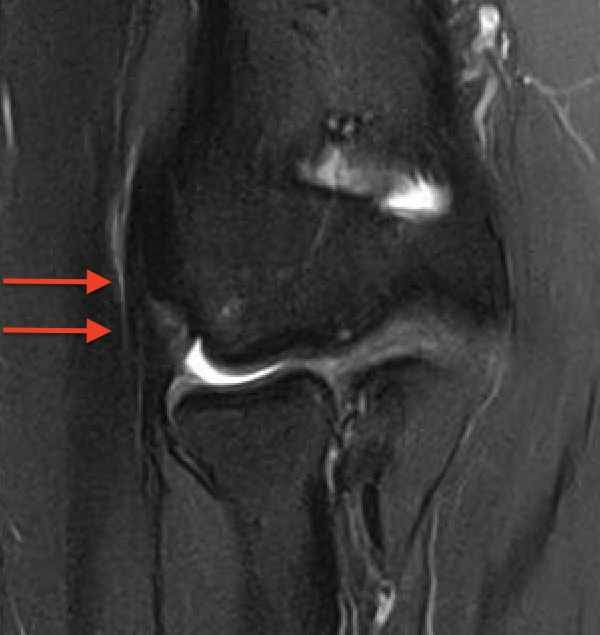

MRI

Normal

PRLI

Subtle instability of the radiocapitellar joint